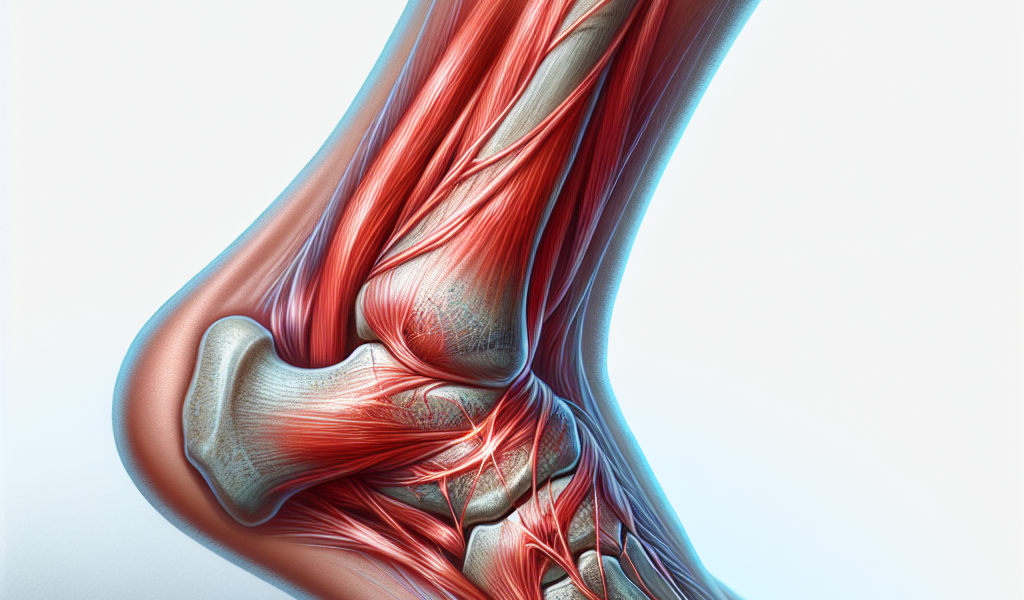

Zwichnięcie i skręcenie stawów to dwa różne urazy, które często mogą być mylone ze względu na podobieństwo objawów. Kluczowym aspektem jest umiejętność rozróżnienia między nimi oraz zastosowanie odpowiedniego postępowania, by zapewnić prawidłowy proces gojenia się i minimalizować ryzyko dalszych komplikacji.

Zwichnięcie to uraz, w którym dochodzi do przemieszczenia się końców kostnych tworzących staw, w rezultacie czego tracą one normalny kontakt. Skręcenie natomiast to uszkodzenie ligamentów, czyli struktur stabilizujących staw – ich nadmierne rozciągnięcie lub rozerwanie. Rozpoznanie, czy doszło do zwichnięcia czy skręcenia, jest ważne dla określenia odpowiedniego sposobu leczenia.

Zwichnięcie – jak rozpoznać?

- Zauważalna deformacja i wyraźne przemieszczenie w obrębie stawu.

- Ostry ból nasilający się przy próbie ruchu stawu.

- Występowanie obrzęku i sinienia wokół stawu.

- Niemożliwość wykonania ruchów stawem.

- Pojawienie się silnych objawów bólowych tuż po urazie.

Skręcenie – charakterystyczne objawy

- Ból w okolicy stawu, który może narastać stopniowo.

- Wystąpienie obrzęku, często po pewnym czasie od urazu.

- Subtelna niestabilność stawu, bez wyraźnej deformacji.

- Zasinienie i zaczerwienienie skóry nad uszkodzonym stawem.

- Ograniczona ruchomość i ból przy nacisku.